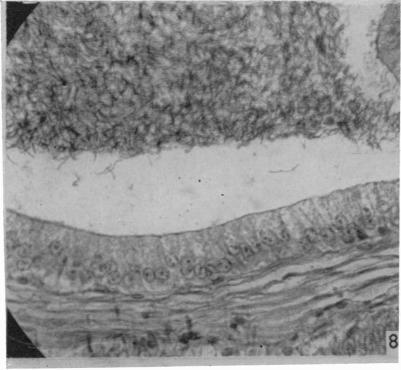

The male reproductive tract of the fowl.

J Anat. 1957 Jan;91(1):116-29.